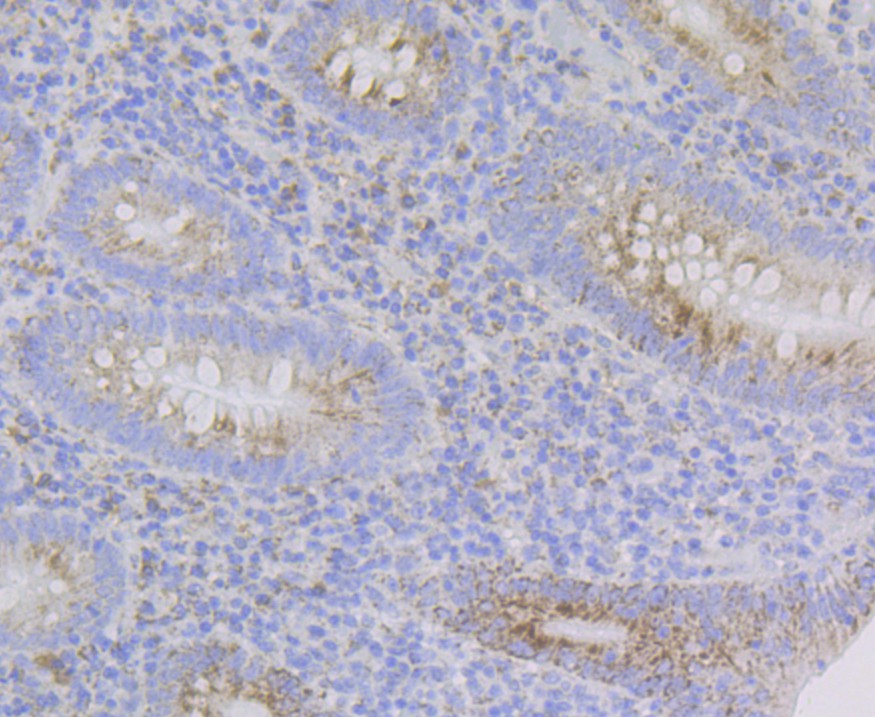

G-protein coupled receptor 30 Rabbit Polyclonal Antibody

IHC-P